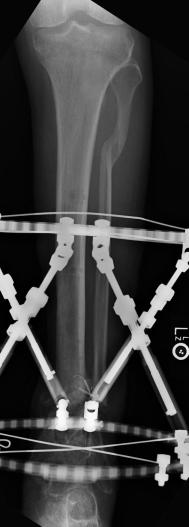

Postoperative (13th) images of left ankle

The image(s) displayed here were created following Liam's 13th surgery which was performed by Dr. Saunders. After a few hiccups getting

the surgery scheduled, Liam spent most of the September 13th afternoon in his 13th surgery. ;-) The surgery lasted about 5 hours and according

to the doctor, it was a good surgery. The 1st photo shows the new frame bracing that holds Liam's ankle together. The next series of photos show

various angles of the ankle and the rods that go from the frame into and through the left ankle. There was some concern that the swelling would

burst and allow for infection. Looks like we are now past that concern. Liam is still on antibiotics to ward of potential infection. The flesh

images show how the skin reacts to having the leg adjusted by the brace. The doctor has had to cut the skin to allow the rods to move freely.